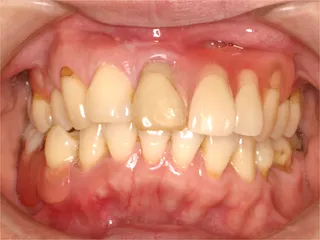

自費によるオプション治療について 保険対応での治療では素材や費用の面で高級な素材や高度先端医療を用いる事が許されていません。

よりよい結果を求めるなら、自費による治療をお薦めいたしますが、その費用が高額になるため気軽に相談しにくいとのご意見を頂戴します。

このページでは、代表的なオプション治療の費用の目安を掲載しております。高度歯科治療をお考えの方は是非ご覧になって参考にしてください。

費用は状態や症状により変動します。状態によっては使用できない素材、治療法もありますので、あらかじめご了承ください。